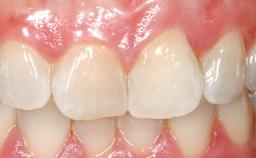

Late Flapless Placement of an Implant in a Maxillary Left Central Incisor Site

| Prosthesis Type | FDP |